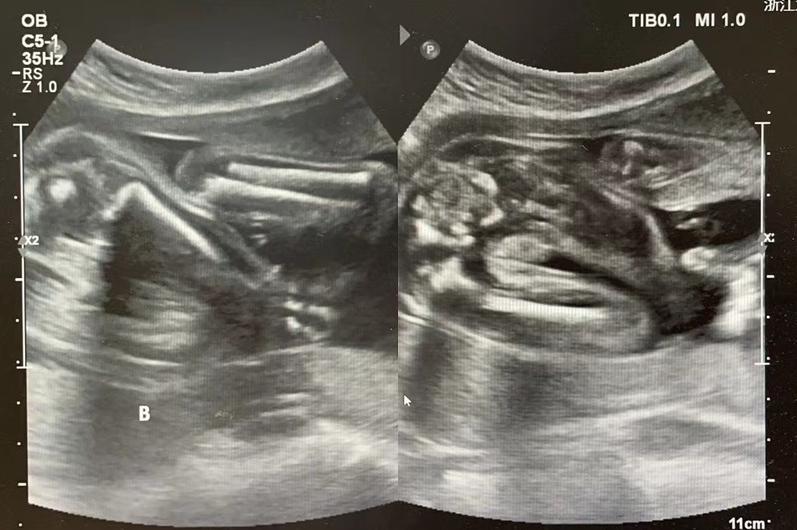

妊娠17周入院时发现A胎羊水极少

浙大妇院的超声显示,这对双胞胎是上下胎位,位于下面的A胎羊水最大深度仅1.3cm,羊水量严重不足;位于上面的B胎羊水最大深度3.5cm,情况还算良好。

每周都给产妇做一次超声,评估B胎儿的生长状况和宫颈长度。

B胎分娩前B超图像